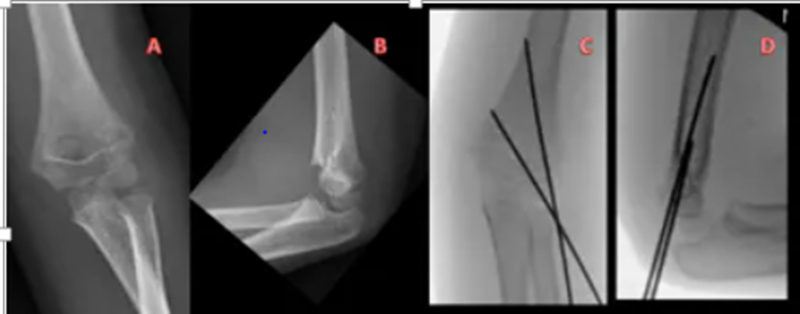

Hình 3.1.2:  A,B :Phim chụp khớp khuỷu ở bệnh nhân nam 5 tuổi gãy trên lồi cầu xương cánh tay Gartland IIb . C,D: Phim sau chụp của cùng bệnh nhân, sử dụng hai đinh Kirschner phía ngoài